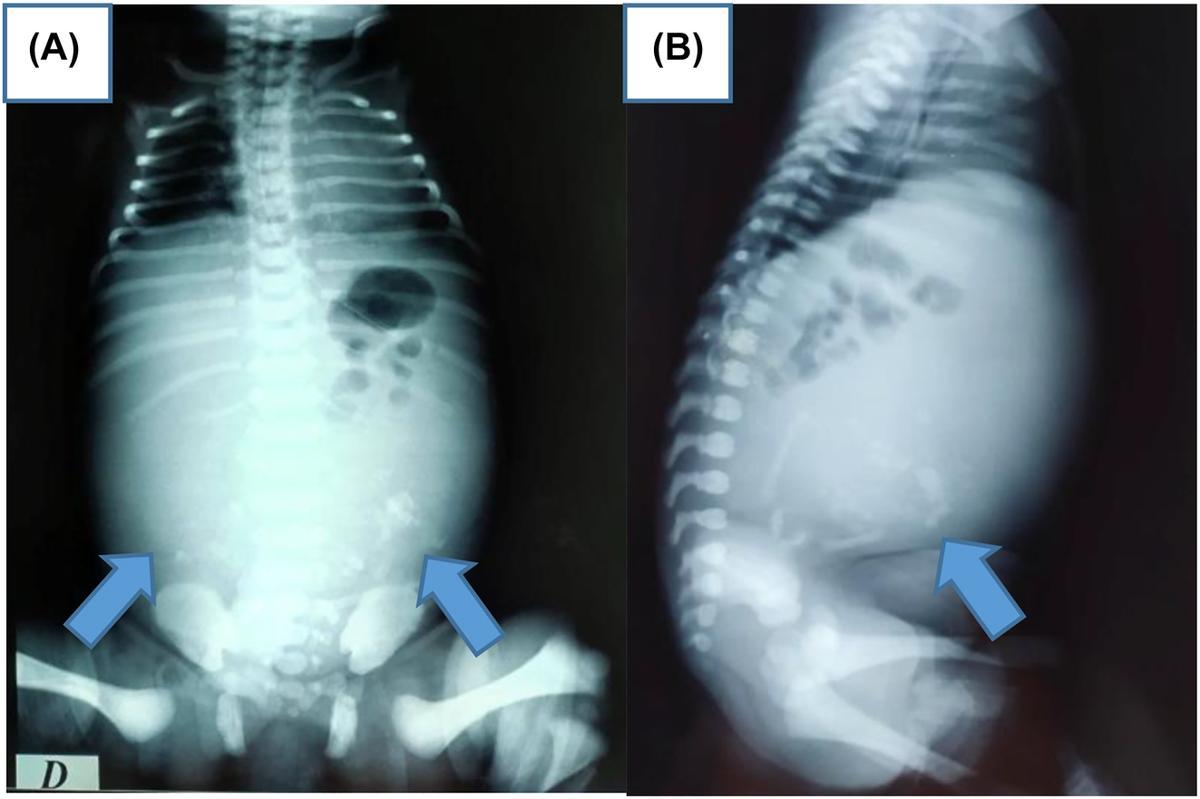

Fetus in feto. / Cedida

En 2024, se publicó el caso de un adolescente de 16 años que acudió al hospital por una masa abdominal y en quien las pruebas de imagen revelaron la presencia de vértebras dentro del cuerpo, un hallazgo extremadamente raro en la adolescencia, ya que la mayoría de los diagnósticos se producen en los primeros años de vida. En otros informes médicos, se describen localizaciones insólitas, como los pocos casos en los que el feto parásito se halló dentro de la cavidad craneal del gemelo portador, algo registrado en apenas dos ocasiones en todo el mundo. Gracias a los avances tecnológicos, también se han identificado diagnósticos prenatales, como el de un embarazo en Turquía en el que una ecografía a las 37 semanas permitió detectar la anomalía antes del nacimiento y proceder a su extracción mediante cirugía.